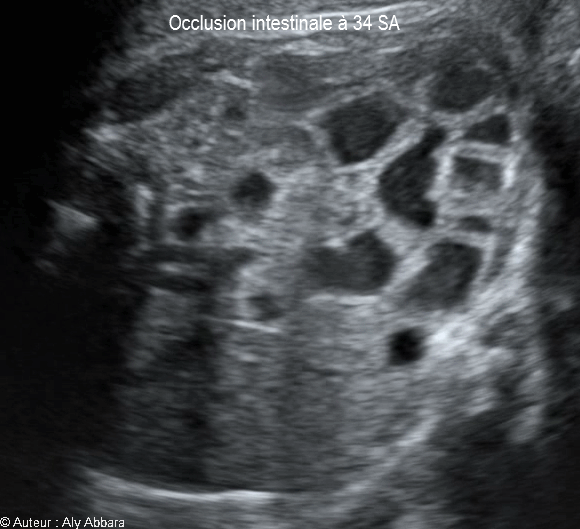

Occlusion intestinale caractérisée par la dilatation des anses grêles et une hyperpéristaltisme : foetus de 34 SA

Images échographiques montrant une occlusion intestinale se manifestant par la dilatation des anses grêles et un hyperpéristaltisme.

Cette occlusion intestinale est liée à la présence, dans la fosse iliaque droite, d'un magma d'anses grêles hyperdenses, agglutinées et obstruées.

L'estomac n'est pas dilaté (occlusion digestive basse), mais on note également l’existence de deux anomalies morphologiques associées :

* Une agénésie du rein droit

* L'absence, au niveau de crosse de l'aorte, de sa 3ème branche, c'est-à-dire l'artère subclavière gauche.

Il s'agit d'une fœtus de 34 SA ; après sa naissance à 38 SA, cette occlusion des anses grêles a nécessité deux interventions chirurgicales digestives dans la période néonatale.